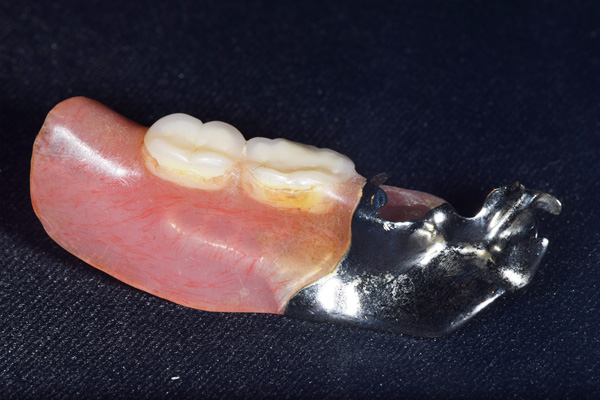

右上と左下の歯がない方です。 上の入れ歯の安定が悪く、作り直したいとのことでいらっしゃいました。 今お使いの上の入れ歯を見てみると、口蓋部分が抜けており、安定性に欠ける構造になっていました。この入れ歯はノンメタルクラスプデンチャーといって、金属のバネを使用しない 入れ歯になります。これは見た目は良いのですが、歯への負担が大きいことと、入れ歯自体がやわらかいため、噛むには不便なことがあります。

入れ歯は極力薄くするために金属を使用しました。しっかり噛める様にするため、ノンメタルクラスプデンチャーにはしませんでした。

下の入れ歯